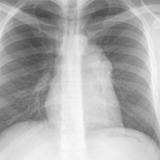

Case 9 Thymoma PA

Date: 04/04/2010

Views: 3167